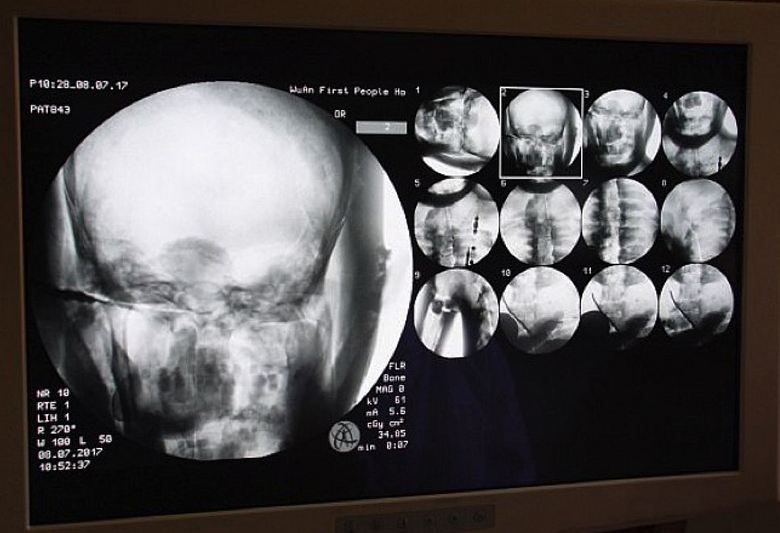

Учените с охота се съгласиха, защото самите те се интересуваха това интересно проучване. И на 8 юли тази година, точно в храма Dinghui, извършена е томография на древната будистка мумия монах. Лекарите докараха тук необходимото оборудване и похарчиха сканиране на вътрешното съдържание на мумията. Бяхме шокирани изключително всичко, тоест не само учени, но и монаси, поклонници, които се събраха на този безпрецедентен за манастира събитието, разбира се, и медийни работници. Оказа се, че ставите, т.е. костите и зъбите на хилядолетен монах Ца Сиан са като тези на жив човек. Нещо повече, мозъкът му беше отлично запазен.

Просто е невероятно, коментира д-р Ву. Yongqing (Wu Yongqing), който директно извърши томография мумии. Не мога дори да повярвам как основните части на човек балсамиран преди повече от хиляда години, запазен в “здравословно” състояние, дори мозъкът! Но самите монаси не са не виждат нищо свръхестествено в това, те са сигурни, че Учителят Ци Сиан изобщо не умря, той просто влезе в състояние на самадхи, от който един ден със сигурност ще се събуди. В крайна сметка сканиране на мумия показа: тялото му е готово за нов живот …